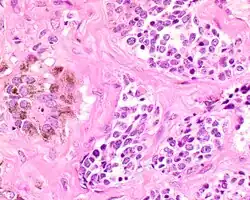

A high power of melanotic neuroectodermal tumor of infancy showing pigmented large epithelioid cells and smaller primitive cells (hematoxylin and eosin stain).

There are centrally located, small, darkly staining cells comprising the majority of cells. These cells have a fibrillary cytoplasm surrounding round nuclei with coarse and heavy nuclear chromatin. These cells are surrounded by much larger polygonal cells that have open nuclear chromatin and abundant opaque cytoplasm that has granular melanin pigment.

A high power of melanotic neuroectodermal tumor of infancy showing pigmented large epithelioid cells and smaller primitive cells in alveolar nests (hematoxylin and eosin stain).

There is usually no hemorrhage, necrosis or increased mitoses.[1][4]